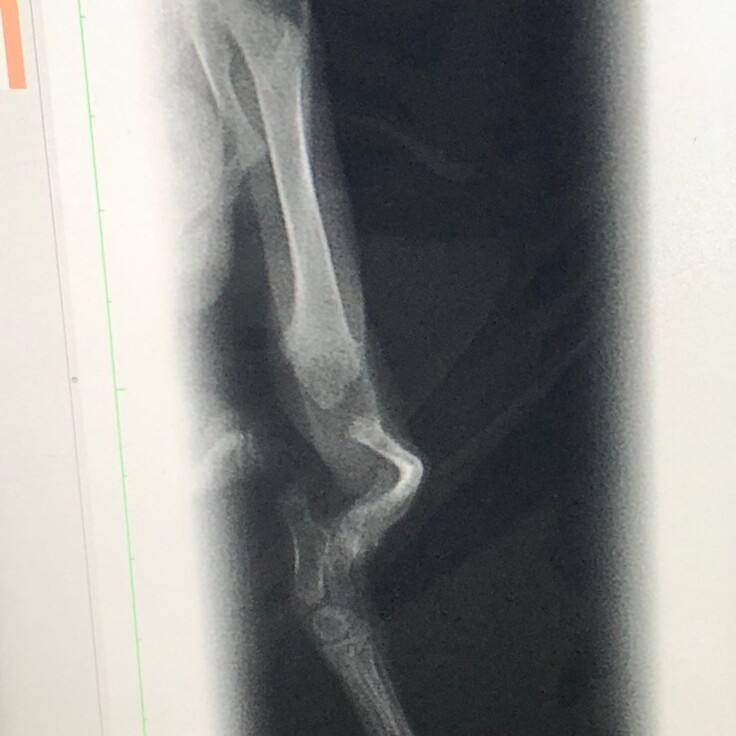

よく見ると足をぶらぶらさせていて、足が不自由なようでした。

足を引きずりながら移動する様子を見て、お外で暮らすことはできないと思いました。

2本あるはずの骨が1本しかない

健康状態のチェックや駆虫で通院するうちに、両後脚に通常あるはずの骨が無い箇所があり、

生まれつき重度の変形があるとわかりました。